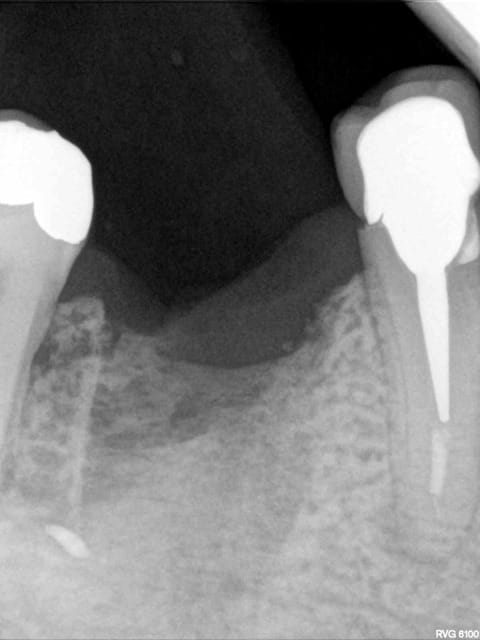

patient qui consulte lundi dernier pour avis implantaire pour 46

je regarde et je vois un petit morceau osseux bien vilain qui dépasse.

l'extraction a eu lieu il y a 4 mois par un confrère qui bosse bien et donc je ne remet pas en cause ses compétences.

je lui ai programmé rapidement une intervention pour ce matin afin de cureter.

il a simplement fallu tirer un peu sur le séquestre

il y a eu comblement osseux avec biooss et mise en place de mucograft seal (peu visible sur la photo) même si c'était PRESQUE pas nécessaire (bretelle et ceinture)